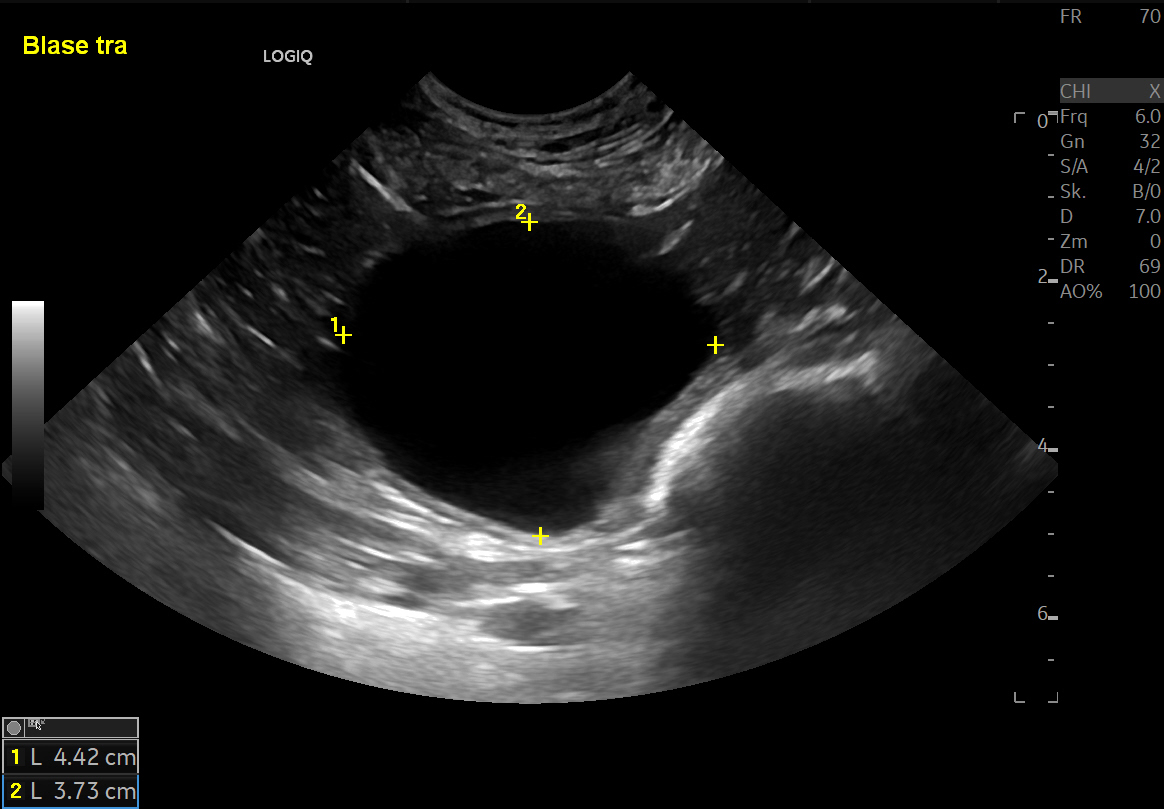

Abdominale Sonografie bei Hund und Katze - Modul 2: Ultraschalluntersuchung von Harnblase, Nieren und Nebennieren

Die sonografische Untersuchung von Harnblase, Nieren und Nebennieren bei Hund und Katze wird jeweils anhand folgender Kriterien ausführlich erklärt und demonstriert

Diagnostik und Management der Harninkontinenz beim Hund

Dieser Fortbildungsartikel fasst anhand der American College of Veterinary Internal Medicine Konsensus-Richtlinien den aktuellen Wissensstand über die Harninkontinenz des Hundes praxisgerecht zusammen. Neben Anatomie und Physiologie wird ausführlich auf die Diagnostik und Therapie eingegangen.

Autor: Dr. Dr. Peter Pantke (AniCura Ahlen, Fachzentrum für Kleintiere)